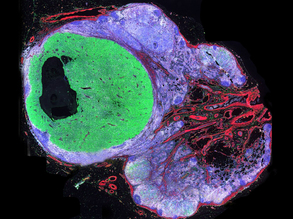

Better Net

Muscle Matrix